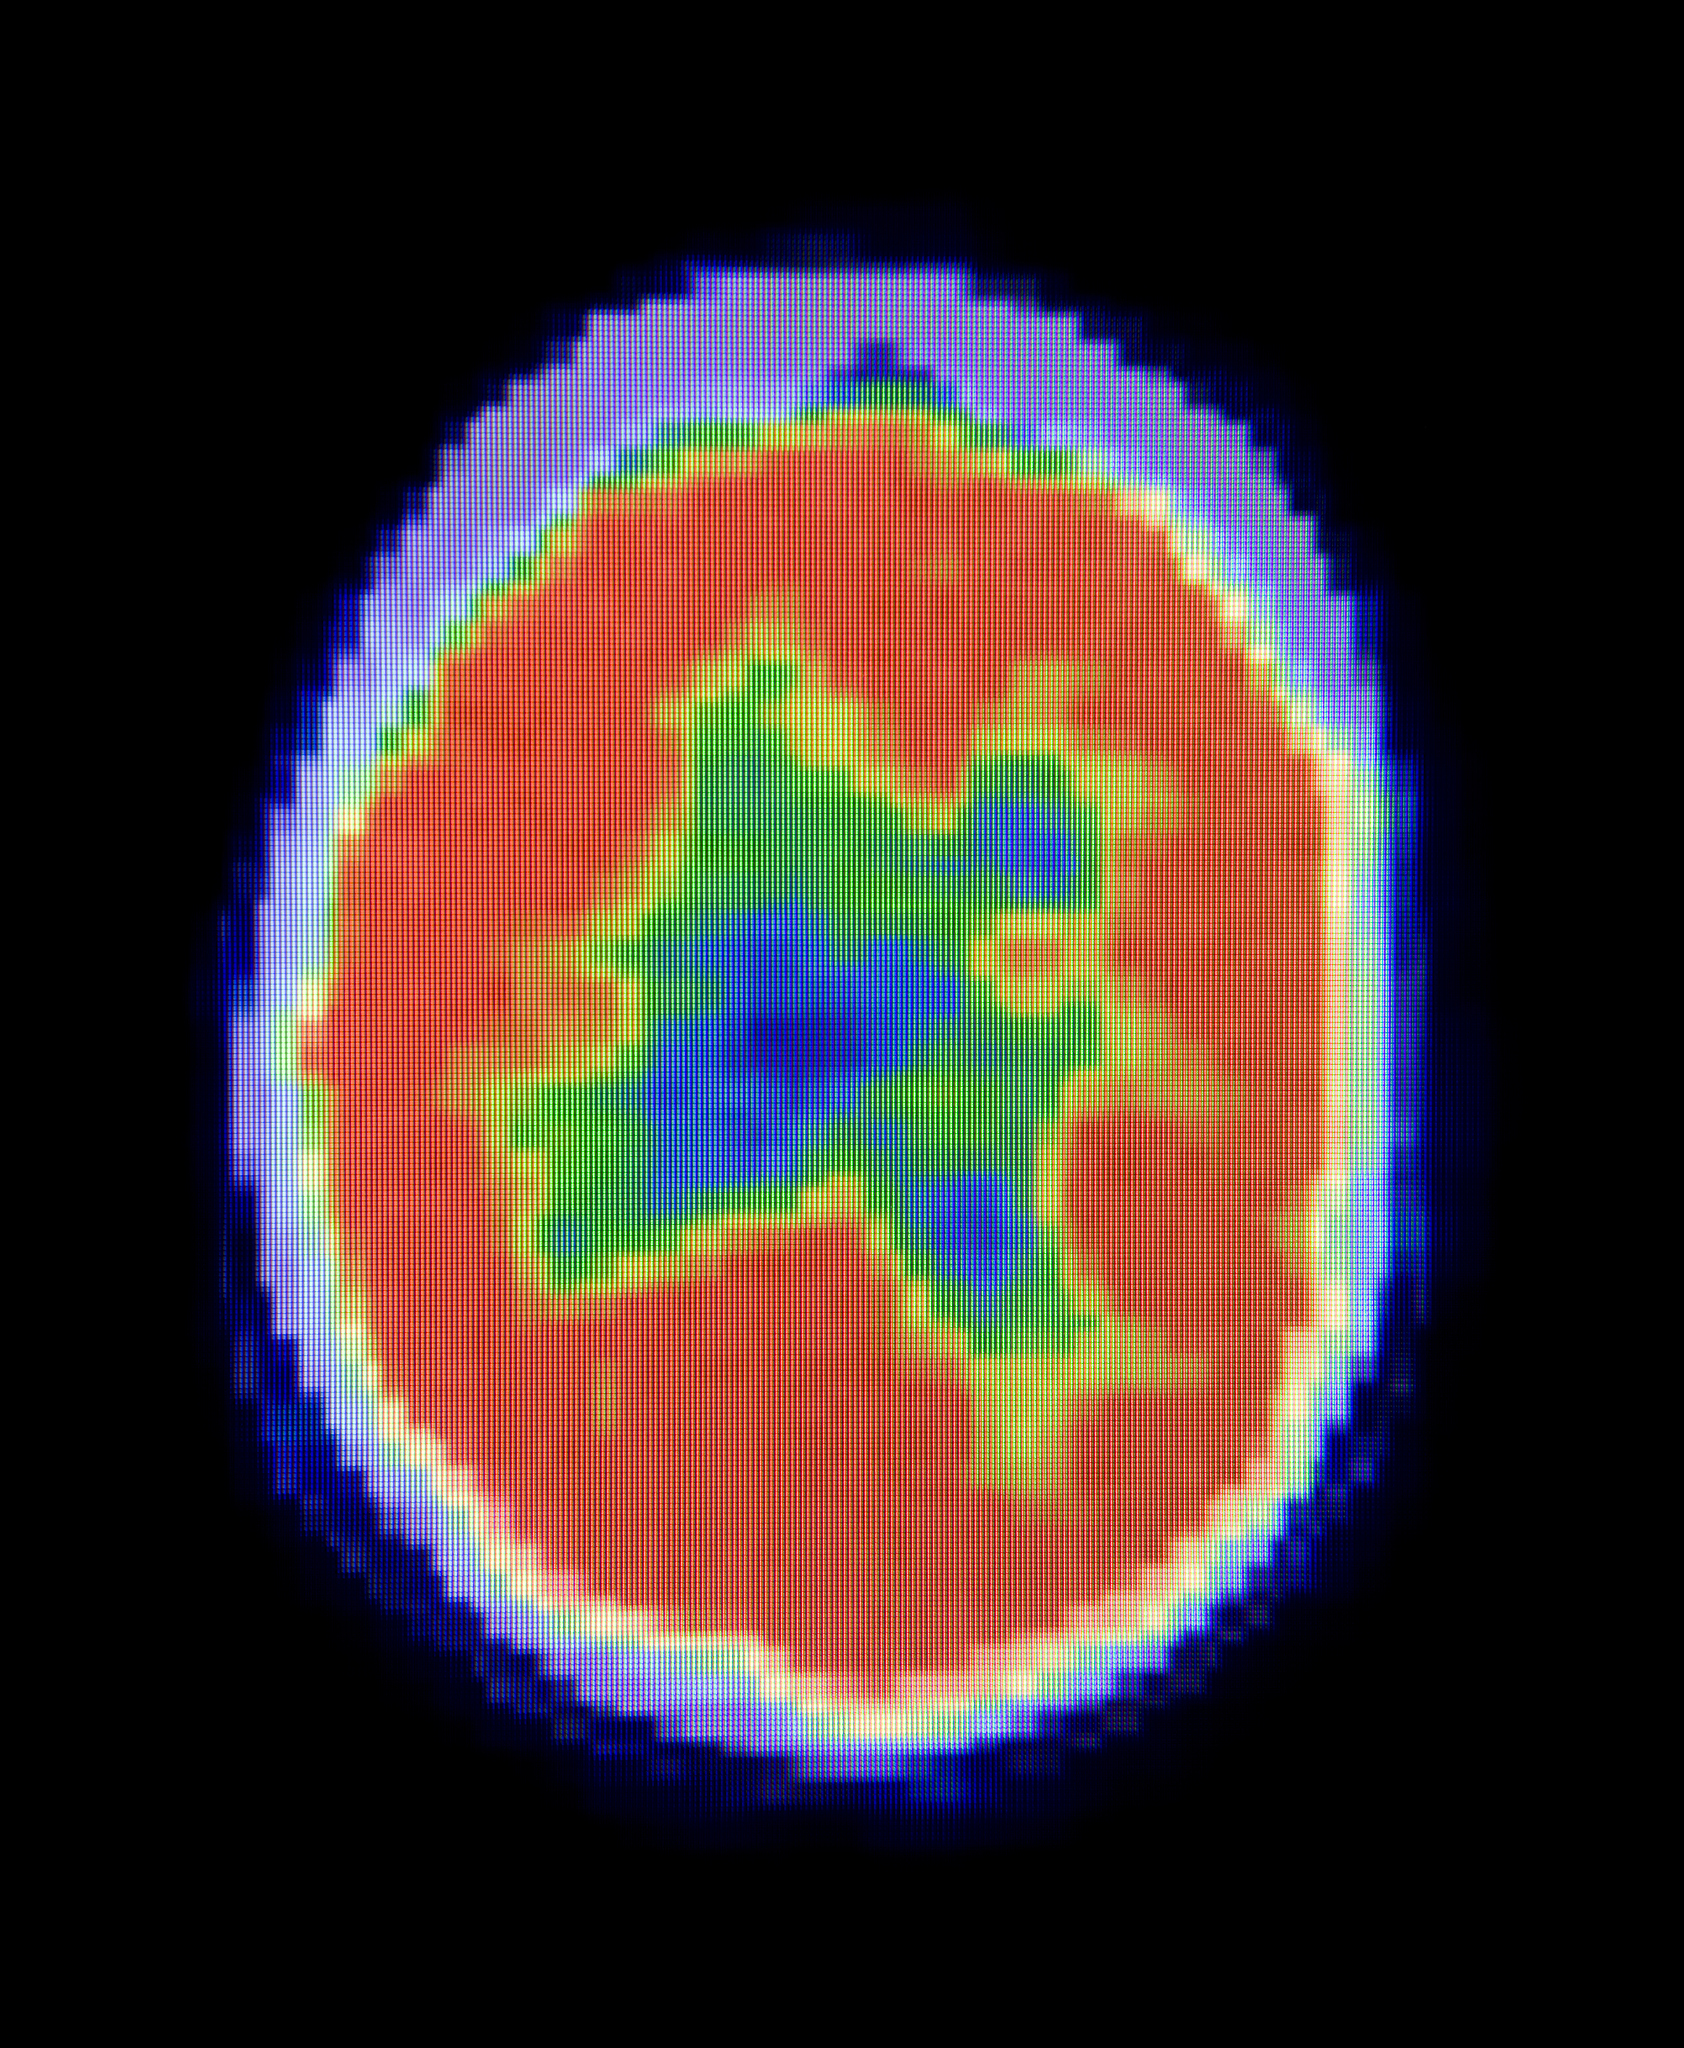

医学影像学是一门涉及医学、物理学、计算机科学等多学科交叉的学科,其研究内容包括医学影像的获取、处理、分析、诊断和治疗等方面。医学影像学技术已成为现代医学诊断和治疗的重要手段,为医学研究和临床实践提供了强有力的支持。

医学影像学的主要研究内容包括医学影像的获取、处理、分析、诊断和治疗等方面。医学影像学技术已成为现代医学诊断和治疗的重要手段,为医学研究和临床实践提供了强有力的支持。在第三军医大学医学影像学专业中,学生将学习医学影像学的基本理论和技术,包括医学影像学的物理学基础、医学影像学的图像处理和分析技术、医学影像学的临床应用等方面。

医学影像学专业是一门涉及医学、物理学、计算机科学等多学科交叉的学科。医学影像学的主要研究内容包括医学影像的获取、处理、分析、诊断和治疗等方面。在医学影像学的研究和应用中,医学影像学的技术已成为现代医学诊断和治疗的重要手段,为医学研究和临床实践提供了强有力的支持。